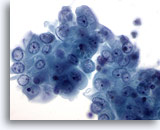

Figure 9: Breast FNA, Fibroadenoma. In this field the edges of the ductal group are not smooth as the previous two images above, possibly due to the liquid-based processing. Within the group of ductal cells, and at the upper edge, a few myoepithelial cells are noted. With ThinPrep processing myoepithelial cells tend to be seen adjacent to the ductal groups rather than scattered in the background as seen in conventional smears. 40x

Figure 9

Breast FNA, Fibroadenoma.

In this field the edges of the ductal group are not smooth as the previous two images above, possibly due to the liquid-based processing. Within the group of ductal cells, and at the upper edge, a few myoepithelial cells are noted. With ThinPrep processing myoepithelial cells tend to be seen adjacent to the ductal groups rather than scattered in the background as seen in conventional smears.

40x